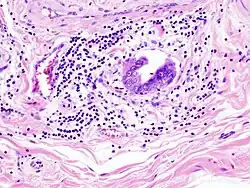

-

Gallbladder adenocarcinoma lymphatic invasion histopathology -